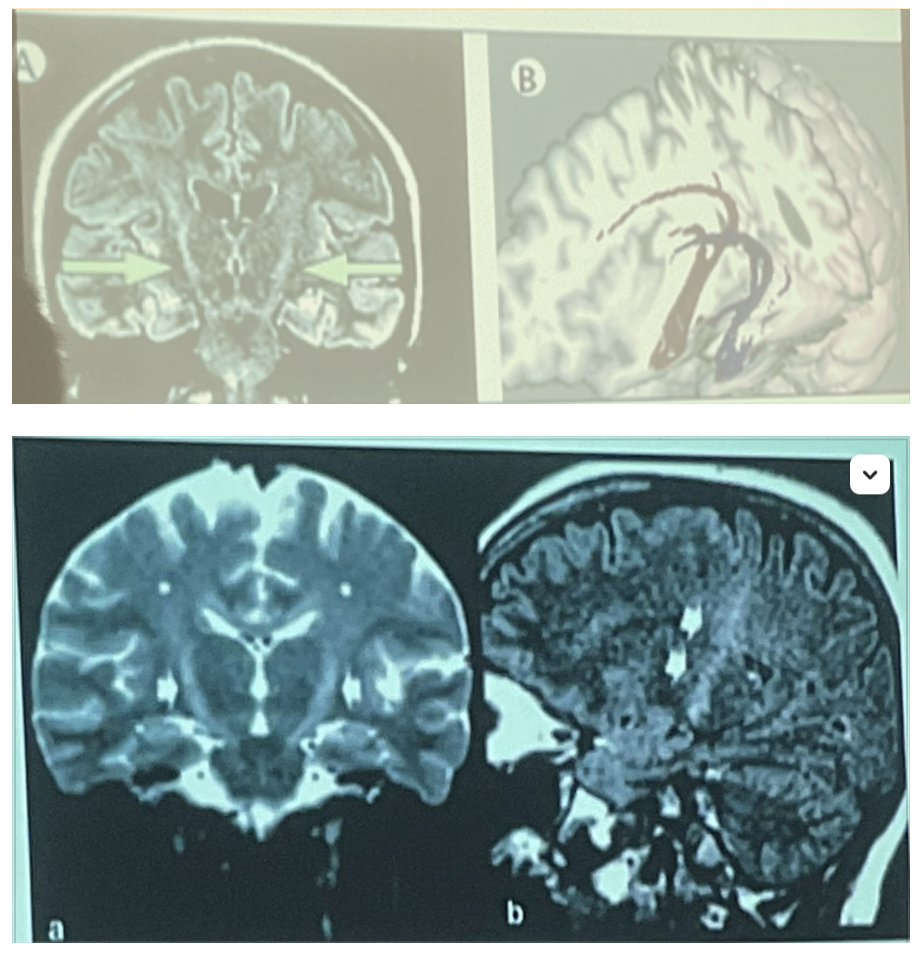

¿Que se ve aqui?

Esclerosis en RM